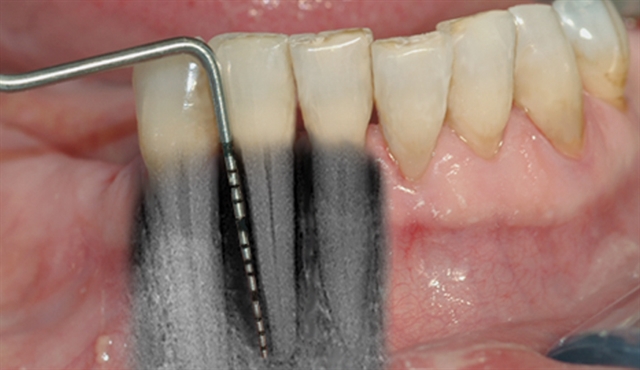

• Biletet viser tilsynelatande normale tannkjøttilhøve ved tenner i underkjeven.

• Ei undersøking med lommeregistrering avdekkjer likevel eit omfattande beintap ved den eine

tanna.